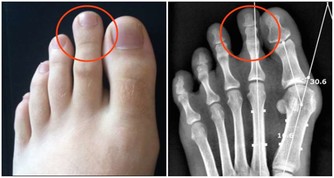

當人出現腳氣、四肢浮腫、消化不良、血壓下降等症狀時,很有可能缺少維生素B1。

維生素B1對於上述的情況有預防作用,需及時補充。

來源:通過食用肉類食物、動物的肝腎或者是小米、豆類食物可以補充維生素B1。